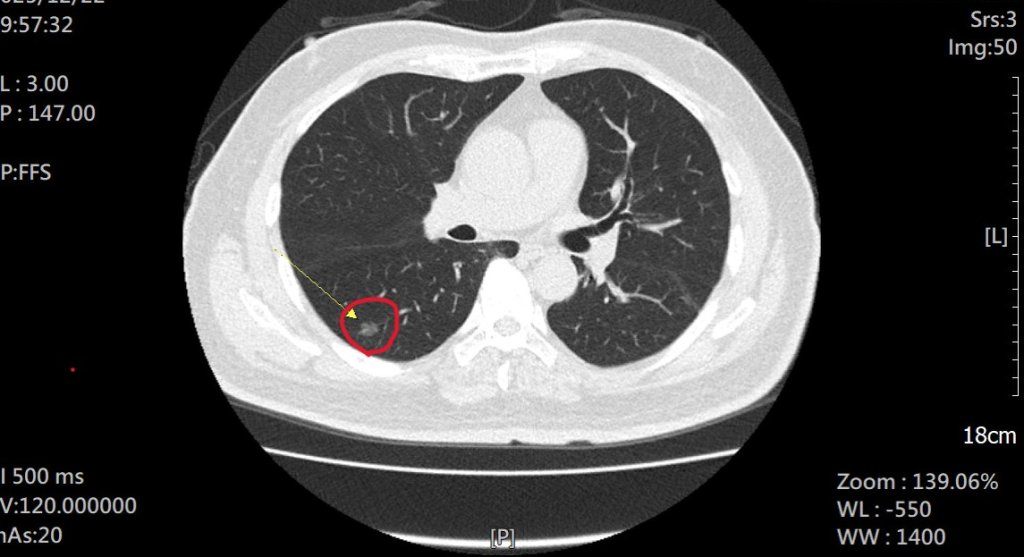

抽菸30多年男子為抱孫子戒菸 並接受LDCT檢查出1期肺癌 術後感謝孫子救了一命

66歲陳姓男子抽菸30餘年,去年年底第一個孫子誕生,他為小嬰兒吸二手菸,決心戒菸,b並前往員榮醫院胸腔內科參加戒菸門診。因符合國健署肺癌補助計畫,接受「低劑量電腦斷層(LDCT)」篩檢,卻意外檢查出右下肺部有一處直徑約 1 公分的毛玻璃狀病變,疑似早期肺腺癌,林鴻慶主任與在駐診員榮醫院的秀傳醫院副院長李佳穎醫師評估後,經手術切除,3天出院,即時撿回一命。-